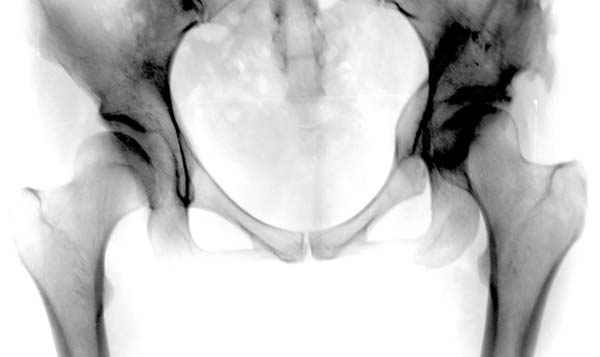

Мною произведены измерения на 290 рентгенограммах ТБС у молодых лиц обоего пола (средний возраст их 26.919 лет) без признаков патологии означенного сустава. Согласно точным расчетам плечо массы тела в среднем составило 107.685 мм (расстояние от центра головки бедренной кости до средней линии тела). Согласно тем же точным расчетам плечо силы реакции связки головки бедра равняется в среднем 35.190 мм (расстояние от центра головки бедренной кости до дна ямки вертлужной впадины, где прикрепляется проксимальный конец связки головки бедра). Соответственно плечо веса тела относится к плечу силы реакции связки головки бедра как 1:3,060, это если быть точным… Я допускаю, что есть проекционные искажения, эффект увеличения изображения на рентгенограмме, погрешности в измерениях, индивидуальная изменчивость размеров, быть может я недостаточное количество суставов обмерил, точку проксимального крепления связки головки бедренной кости на рентгенограмме не видно, а линия действия ОЦМ в одноопорном ортостатическом положении смещается от центра в сторону ТБС на разную величину, обусловленную антропометрическими особенностями и т.д.… именно поэтому в своем сообщении я указал соотношение 1:3, и назвал его приблизительным».